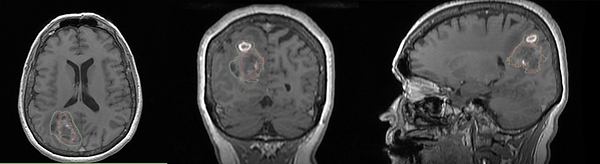

Figure 4 shows an example of a false negative tumor segmentation, which can be improved with the Shape Edit feature

Figure 4: Tumor segmentation showing the ground truth in green and the prediction in red. The transversal, coronal and axial direction of the source Dicom are centered on the right parietal tumor. The contrast uptake of the tumor is low and therefore there is a significant false negative part. Editing the shape could be a good option in this patient.